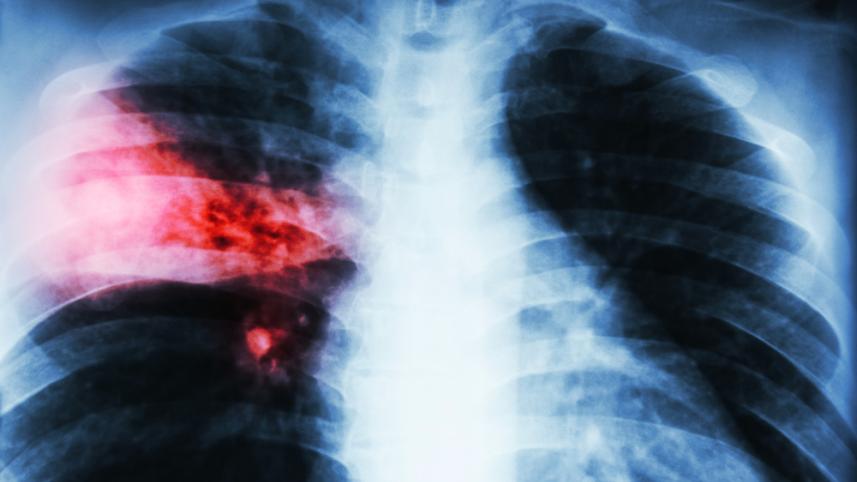

অধ্যাপক সোহেল মাহমুদ বলেন, নিউমোনিয়া এক ধরনের মারাত্মক সংক্রমণ যা ফুসফুসকে আক্রান্ত করে। বিভিন্ন ধরনের জীবাণু, কিছু ভাইরাস, ব্যাকটেরিয়া এবং ছত্রাকের সংক্রমণে নিউমোনিয়া হয়। বেশিরভাগ ক্ষেত্রে ভাইরাস ও ব্যাকটেরিয়ার সংক্রমণ থেকে নিউমোনিয়া হয়। নানা রকম ব্যাকটেরিয়া বাতাসে ঘুরে বেড়ায় এবং তা ফুসফুসে প্রবেশ করলে সংক্রমণ থেকে নিউমোনিয়ার উৎপত্তি হয়। এতে ফুসফুসের ভেতর এয়ার স্যাকগুলো সংক্রমণের কারণে প্রদাহগ্রস্থ হওয়ায় ফ্লুইড বা তরল জমে যায়। তখন অক্সিজেন ঠিকমত যেতে পারে না এবং শ্বাস-প্রশ্বাসে সমস্যা হয়।

অধ্যাপক সোহেল মাহমুদ বলেন, জ্বর, কাশি, বুকে ব্যথা এবং কফ হলুদ হয়ে যাচ্ছে এমন লক্ষণ দেখা দিলে অবশ্যই চিকিৎসকের পরামর্শ নিতে হবে। সাধারণত রক্ত পরীক্ষা ও বুকের এক্স-রে করাই যথেষ্ট নিউমোনিয়া রোগ নির্ণয়ের জন্য। নিউমোনিয়া দ্রুত নির্ণয় করে চিকিৎসা শুরু করা গেলে সিভিয়ার হওয়ার আশঙ্কাও কমে যাবে।